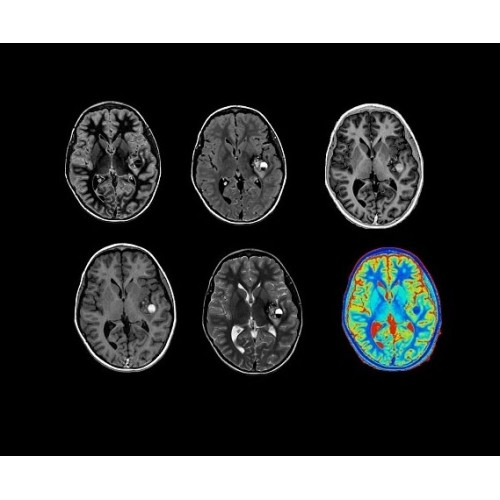

• NeuroWorks — универсальное решение для визуализации анатомии головного мозга, позвоночника, сосудов и периферических нервов с четкой дифференциацией тканей.